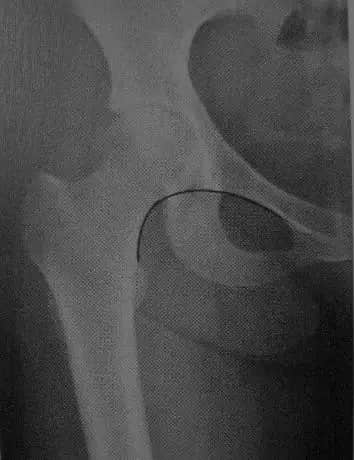

1 股骨颈干角

在髋关节正位片上,股骨干和股骨颈轴线的交角。正常值110-140度,大于140,髋外翻,小于110,髋内翻。